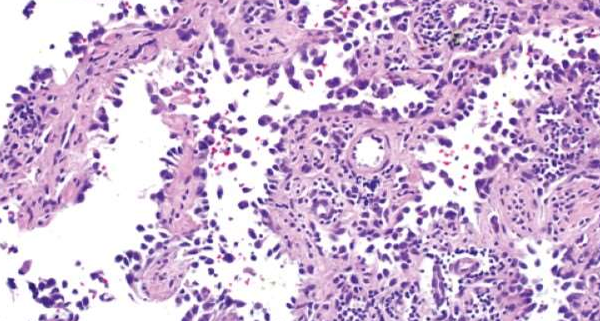

Non RH Endocarditis: Infective Bacterial

The vegetations of BE consist of 3 zones:

i) Outer cap consists of eosinophilic material composed of fibrin and platelets.

ii) Middle basophilic zone containing colonies of bacteria.

iii) Deeper zone consists of non-specific inflammatory reaction in the cusp itself